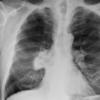

Radiation case 2

Date: 07/30/2005

Views: 3494